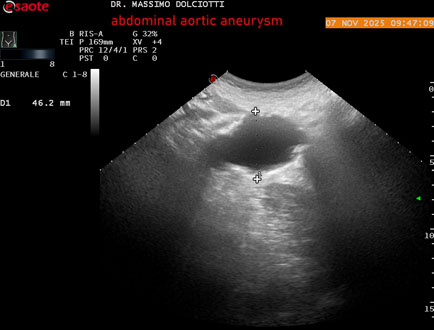

Data inserimento: 11/11/2025

Ecografia del: 07/11/2025

Strumento: Esaote MyLab Eight

Sonda: Convex Multifrequenza 1-8 MHz

Età Paziente: M 60 anni

Motivazione dell'esame: follow up per aneurisma dell'aorta addominale.

Commento all'esame: le immagini ed il video documentano la presenza dell'aneurisma dell'aorta addominale sotto-renale, con diametro antero-posteriore massimo documentato di 47 / 48 mm.

Conclusioni: aneurisma dell'aorta addominale in follow up (abdominal aortic aneurysm follow-up).

Presentazione: Dr. Massimo Dolciotti - Ancona